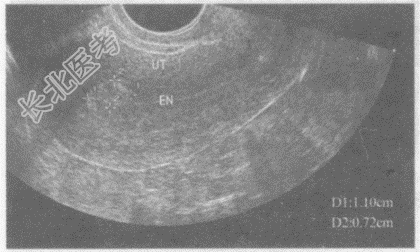

- 单项选择题临床资料:女性患者, 23岁,自述药流术后19天, 阴道出血。

超声综合描述:子宫形态饱满, 宫腔内见1.1cm×0.8cm中强回声区,边界不清晰, 内回声不均,CDFI: 内可见血流信号。见下图及彩图。